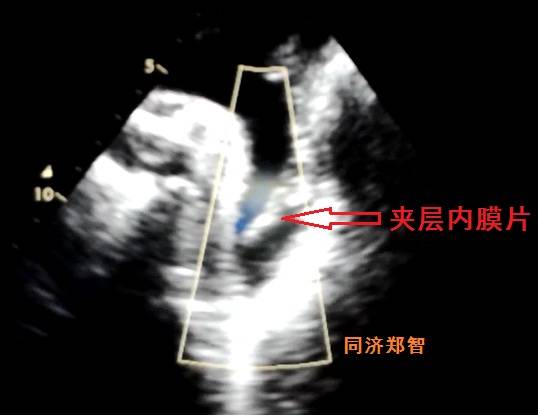

有时在彩超中也可以观察到内膜片,但其准确性不高,存在假阴性和假阳性的可能。